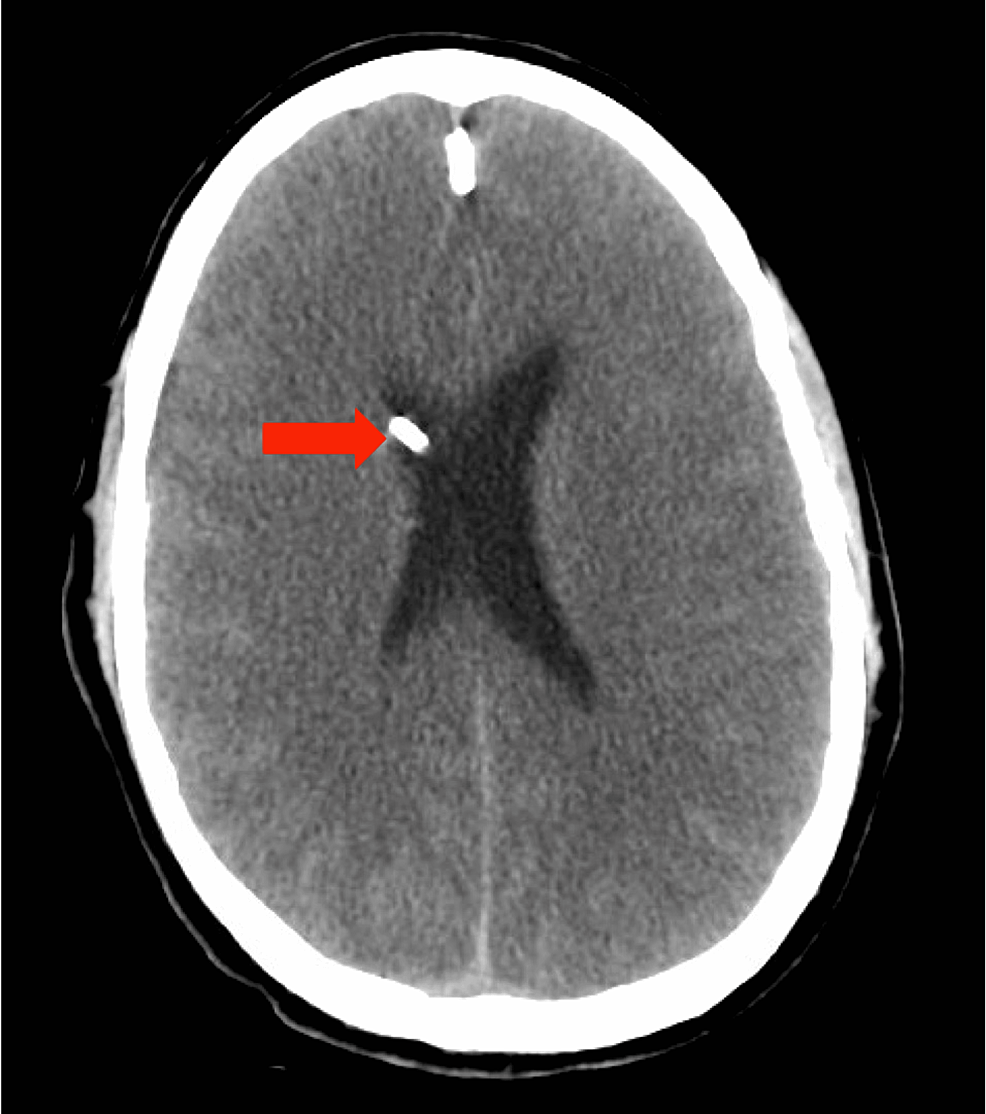

Case 252: Acute Hyperammonemic Encephalopathy Resulting from Late-Onset Ornithine Transcarbamylase DeficiencyRadiology

Case 252: Acute Hyperammonemic Encephalopathy Resulting from Late-Onset Ornithine Transcarbamylase Deficiency | Radiology